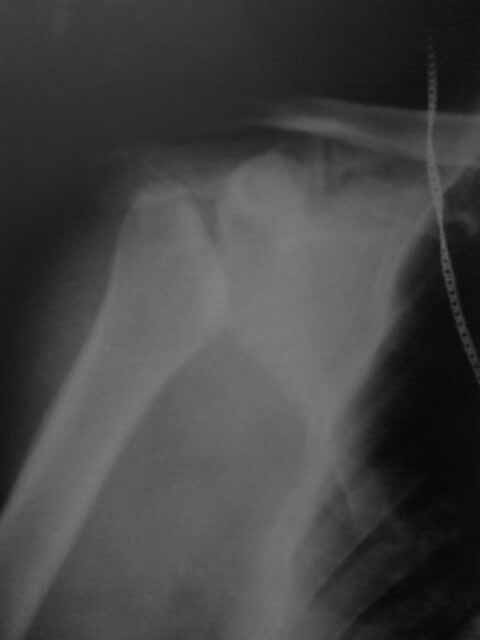

Здравствуйте, коллеги! Помогите пожалуйста определиться с тактикой лечения. Обратился Больной А. 49 л с жалобами на боли в левом плечевом суставе и ограничение движений. Работает оператором КиПа.

считает себя больным С 2010Г, Когда при незначительной нагрузке появились боли в левом плечевом суставе и отек. при первичном обращении выполнялась пункция плечевого сустава, получено - лизированная кровь. На рентгенограммах описывали: асептический некроз головки плечевой кости. За медицинской помощью не обращался. На данный момент: незначительное органичение движений в плечевом суставе, без чувствительных и двигательных расстройств. при пункции прозрачная синовиальная жидкость.Хотелось бы узнать ваше мнение по поводу тактики. Консервативное: купирование синовита с введением sol.kenologi. или если возможно оперативное лечение...артродез плечевого сустава?Заранее благодарю =)

Типичная для сирингомиелии артропатия. Подробнее можно почитать тут.